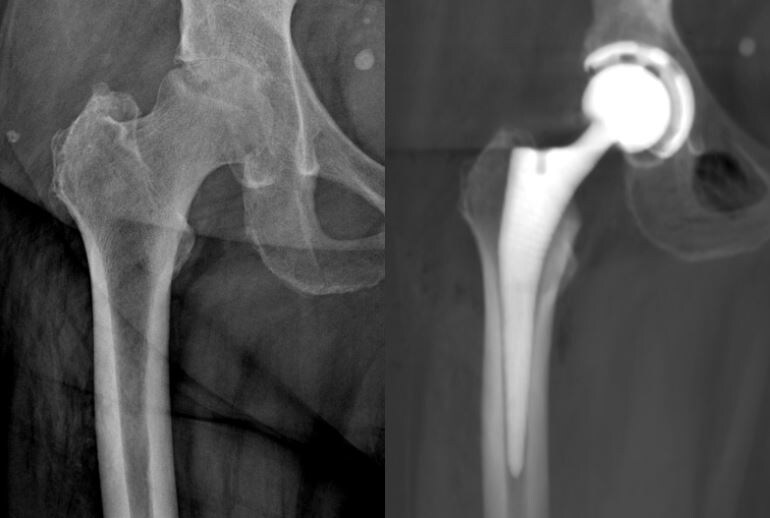

На ΠΊΠΎΠ½ΡΡƒΠ»ΡŒΡ‚Π°Ρ†ΠΈΡŽ ΠΎΠ±Ρ€Π°Ρ‚ΠΈΠ»Π°ΡΡŒ ΠΏΠ°Ρ†ΠΈΠ΅Π½Ρ‚ΠΊΠ° с Π²Ρ‹Ρ€Π°ΠΆΠ΅Π½Π½Ρ‹ΠΌΠΈ болями Π² области Ρ‚Π°Π·ΠΎΠ±Π΅Π΄Ρ€Π΅Π½Π½ΠΎΠ³ΠΎ сустава, Π²Ρ‹Π·Π²Π°Π½Π½Ρ‹ΠΌΠΈ Π½Π΅ΠΊΡ€ΠΎΠ·ΠΎΠΌ Π³ΠΎΠ»ΠΎΠ²ΠΊΠΈ Π±Π΅Π΄Ρ€Π΅Π½Π½ΠΎΠΉ кости. Π‘ΠΎΠ»ΠΈ Π²ΠΏΠ΅Ρ€Π²Ρ‹Π΅ появились послС лСчСния коронавирусной ΠΈΠ½Ρ„Π΅ΠΊΡ†ΠΈΠΈ большими Π΄ΠΎΠ·Π°ΠΌΠΈ стСроидных ΠΏΡ€Π΅ΠΏΠ°Ρ€Π°Ρ‚ΠΎΠ², ΠΈ со Π²Ρ€Π΅ΠΌΠ΅Π½Π΅ΠΌ эти Π±ΠΎΠ»ΠΈ лишили Π΅Ρ‘ возмоТности Π±Ρ‹Ρ‚ΡŒ Π°ΠΊΡ‚ΠΈΠ²Π½ΠΎΠΉ ΠΈ Π΄Π°ΠΆΠ΅ ΡΠ°ΠΌΠΎΡΡ‚ΠΎΡΡ‚Π΅Π»ΡŒΠ½ΠΎ Ρ…ΠΎΠ΄ΠΈΡ‚ΡŒ. На ΠΊΠΎΠ½ΡΡƒΠ»ΡŒΡ‚Π°Ρ†ΠΈΡŽ ΠΎΠ½Π° ΠΊ Π½Π°ΠΌ ΠΏΡ€ΠΈΠ±Ρ‹Π»Π° Π½Π° сидячСй коляскС.

Помимо ΠΏΡ€ΠΎΠ±Π»Π΅ΠΌ с Ρ‚Π°Π·ΠΎΠ±Π΅Π΄Ρ€Π΅Π½Π½Ρ‹ΠΌ суставом, ΠΏΠ°Ρ†ΠΈΠ΅Π½Ρ‚ΠΊΠ° страдала ΠΌΠΎΡ€Π±ΠΈΠ΄Π½Ρ‹ΠΌ ΠΎΠΆΠΈΡ€Π΅Π½ΠΈΠ΅ΠΌ Ρ‚Ρ€Π΅Ρ‚ΡŒΠ΅ΠΉ стСпСни (ИМВ – 43), Ρ‡Ρ‚ΠΎ фактичСски создавало Π·Π°ΠΌΠΊΠ½ΡƒΡ‚Ρ‹ΠΉ ΠΊΡ€ΡƒΠ³ ΠΈΠ· Π³ΠΈΠΏΠΎΠ΄ΠΈΠ½Π°ΠΌΠΈΠΈ ΠΈ ΠΈΠ·Π±Ρ‹Ρ‚ΠΎΡ‡Π½ΠΎΠΉ массы Ρ‚Π΅Π»Π°.

Π’ Ильинской Π±ΠΎΠ»ΡŒΠ½ΠΈΡ†Π΅ благодаря Π²Ρ€Π°Ρ‡Π°ΠΌ ΠΎΠ±Ρ‰Π΅ΠΉ ΠΏΡ€Π°ΠΊΡ‚ΠΈΠΊΠΈ, анСстСзиологам ΠΈ Π³Ρ€Π°ΠΌΠΎΡ‚Π½ΠΎ составлСнному ΠΈΠΌΠΈ ΠΈΠ½Π΄ΠΈΠ²ΠΈΠ΄ΡƒΠ°Π»ΡŒΠ½ΠΎΠΌΡƒ ΠΏΠ»Π°Π½Ρƒ ΠΏΡ€Π΅Π΄ΠΎΠΏΠ΅Ρ€Π°Ρ†ΠΈΠΎΠ½Π½ΠΎΠ³ΠΎ обслСдования ΠΌΡ‹ смогли ΠΏΠΎΠ΄Π³ΠΎΡ‚ΠΎΠ²ΠΈΡ‚ΡŒ ΠΏΠ°Ρ†ΠΈΠ΅Π½Ρ‚ΠΊΡƒ ΠΊ Ρ…ΠΈΡ€ΡƒΡ€Π³ΠΈΠΈ, ΠΈ Π² Π½Π°Π·Π½Π°Ρ‡Π΅Π½Π½Ρ‹ΠΉ дСнь ΠΎΡΡƒΡ‰Π΅ΡΡ‚Π²ΠΈΡ‚ΡŒ Π·Π°Π΄ΡƒΠΌΠ°Π½Π½ΠΎΠ΅. ΠŸΡ€ΠΈΠΌΠ΅Π½ΠΈΠ² соврСмСнный ΠΌΠΈΠ½ΠΈ-ΠΈΠ½Π²Π°Π·ΠΈΠ²Π½Ρ‹ΠΉ способ Ρ…ΠΈΡ€ΡƒΡ€Π³ΠΈΠΈ, ΠΌΡ‹ смогли Π²Π΅Ρ€Π½ΡƒΡ‚ΡŒ Π΅ΠΉ Π²ΠΎΠ·ΠΌΠΎΠΆΠ½ΠΎΡΡ‚ΡŒ Ρ…ΠΎΠ΄ΠΈΡ‚ΡŒ. Π£ΠΆΠ΅ Π² ΠΏΠ΅Ρ€Π²Ρ‹Π΅ сутки послС ΠΎΠΏΠ΅Ρ€Π°Ρ†ΠΈΠΈ ΠΎΠ½Π° вновь смогла Π²ΡΡ‚Π°Ρ‚ΡŒ ΠΈ Π΄Π΅Π»Π°Ρ‚ΡŒ ΠΏΠ΅Ρ€Π²Ρ‹Π΅ шаги ΡƒΠΆΠ΅ Π±Π΅Π· Π±ΠΎΠ»ΠΈ, ΠΈ Ρ‡Π΅Ρ€Π΅Π· нСсколько Π΄Π½Π΅ΠΉ ΠΎΠ½Π° Π±Π»Π°Π³ΠΎΠΏΠΎΠ»ΡƒΡ‡Π½ΠΎ Π±Ρ‹Π»Π° выписана Π΄ΠΎΠΌΠΎΠΉ.